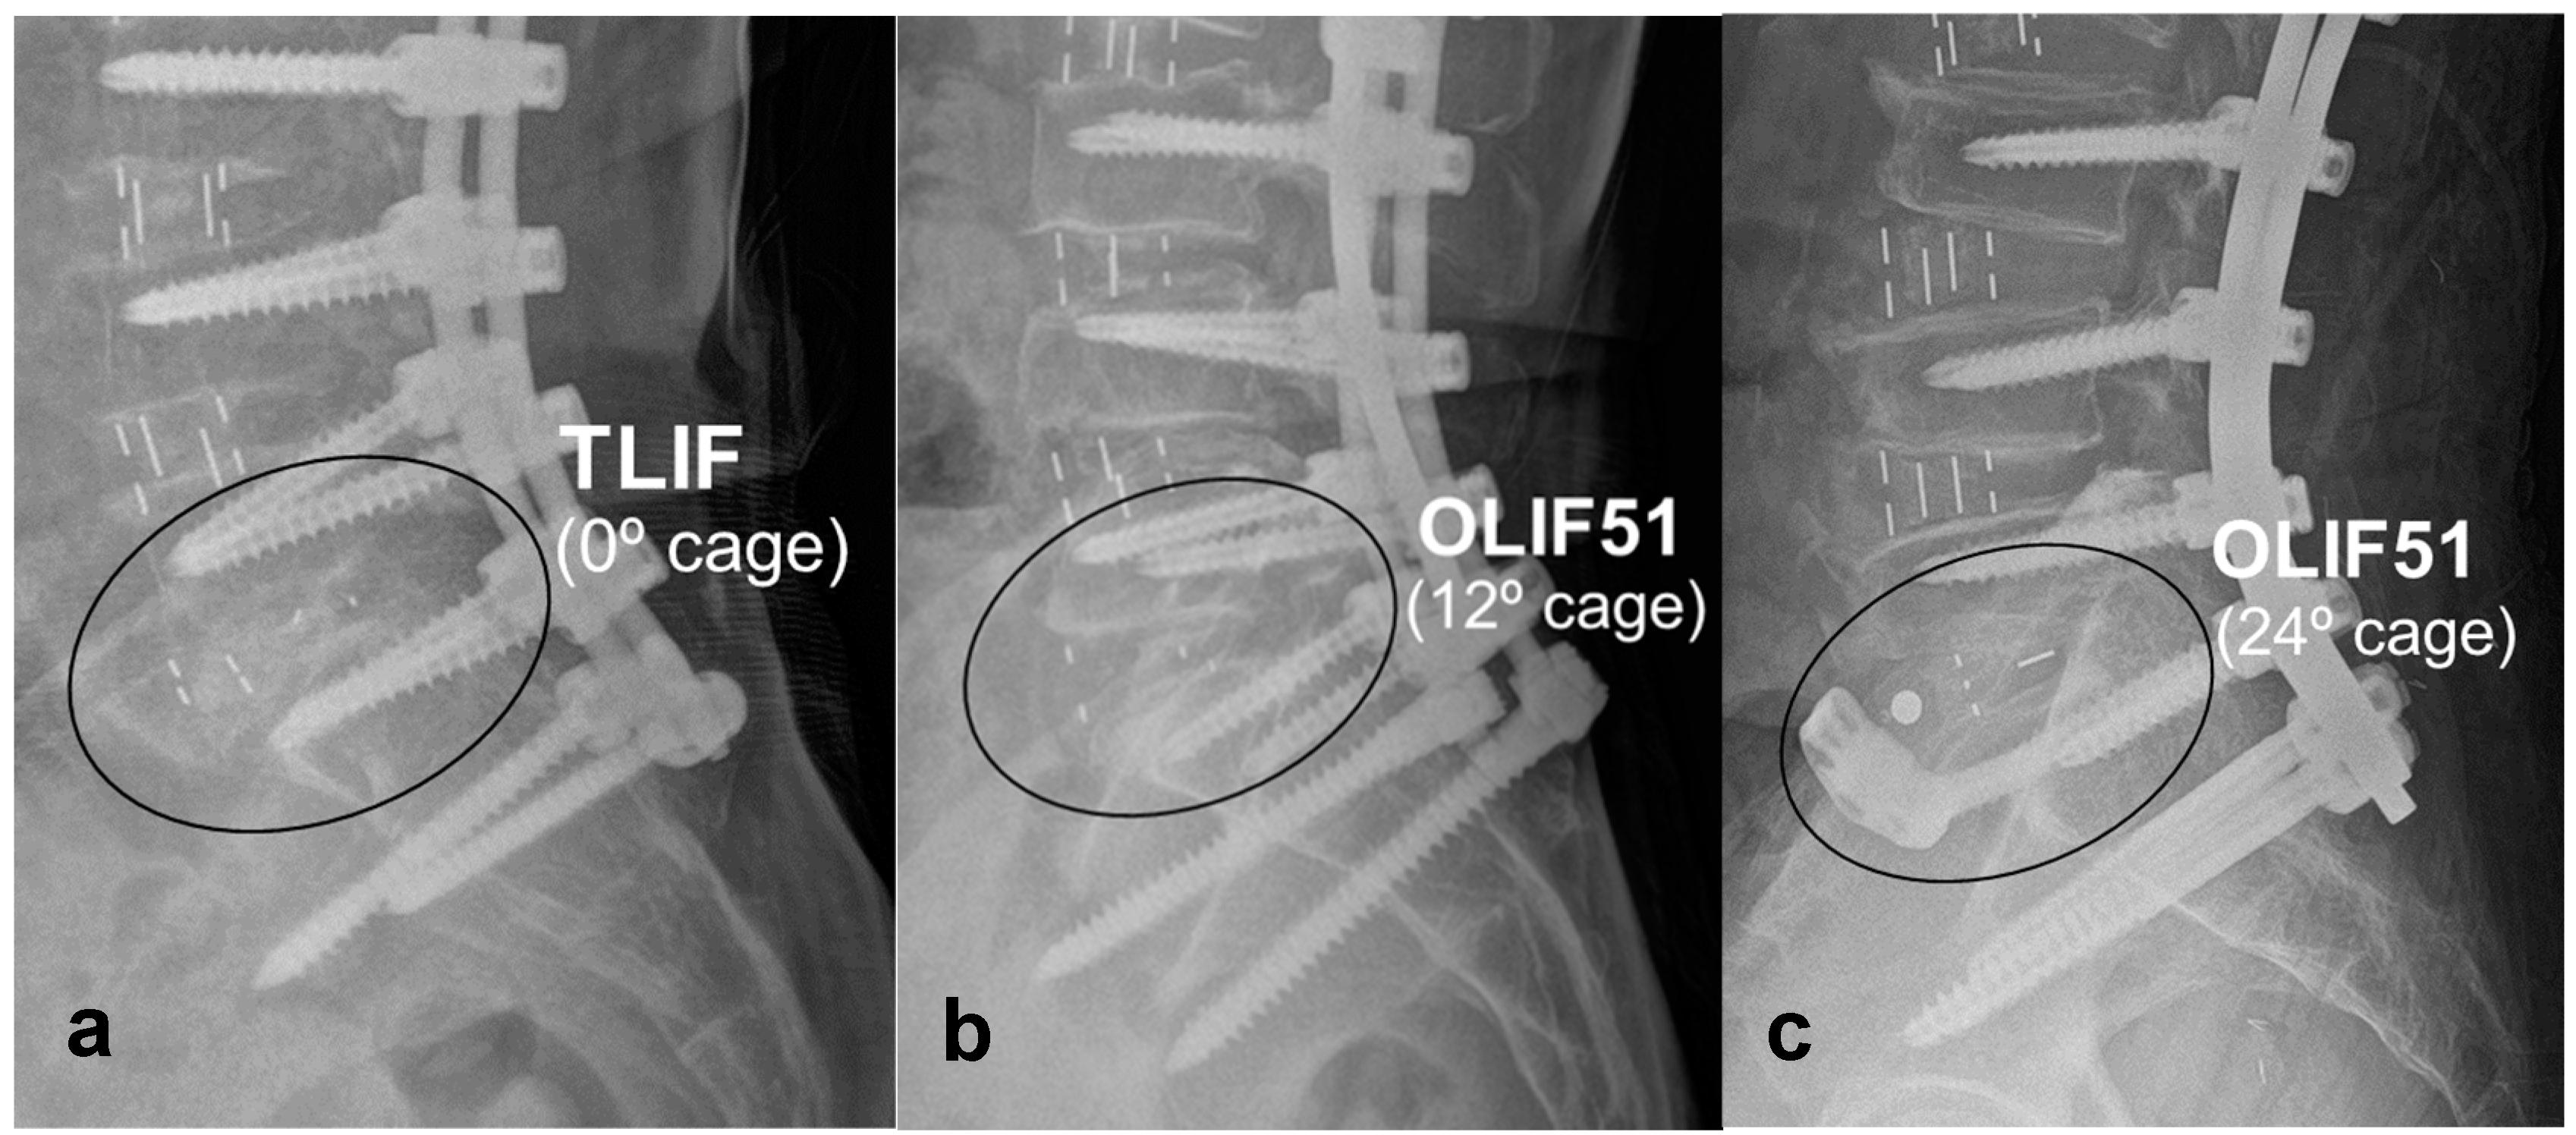

- Ko, M.J.; Park, S.W.; Kim, Y.B. Effect of cage in radiological differences between direct and oblique lateral interbody fusion techniques. J Korean Neurosurg Soc 2019, 62, 432–441. [Google Scholar] [CrossRef]

- Ko, M.J.; Park, S.W.; Kim, Y.B. Correction of spondylolisthesis by lateral lumbar interbody fusion compared with transforaminal lumbar interbody fusion at L4-5. J Korean Neurosurg Soc 2019, 62, 422–431. [Google Scholar] [CrossRef] [PubMed]

- Mun, H.Y.; Ko, M.J.; Kim, Y.B.; Park, S.W. Usefulness of oblique lateral interbody fusion at L5-S1 level compared to transforaminal lumbar interbody fusion. J Korean Neurosurg Soc 2020, 63, 723–729. [Google Scholar] [CrossRef] [PubMed]